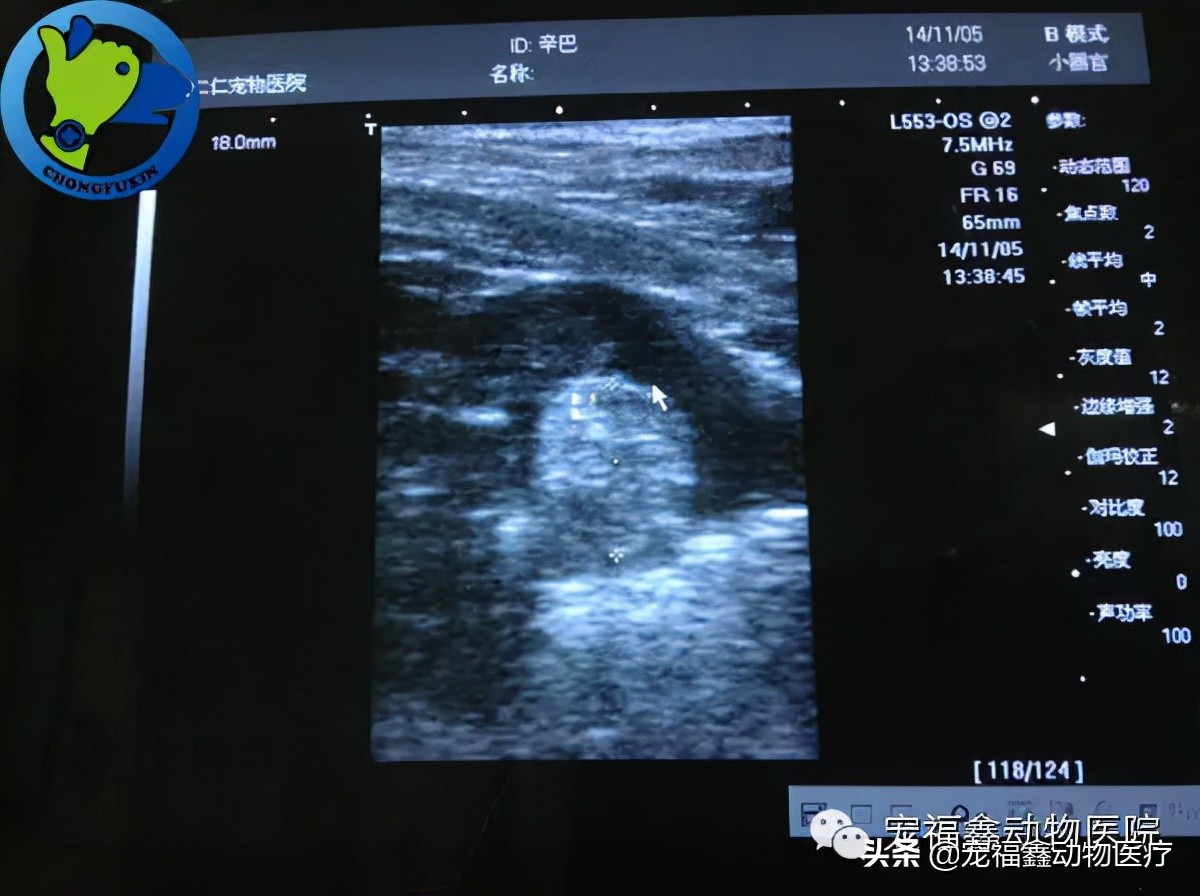

根据经验,接诊的拱海鸥大夫和张文学大夫给辛巴做了一系列检查。初步诊断为前列腺炎,并住院观察,进行输液治疗。一周以后,炎症虽然大幅消退,但临床症状未见明显好转。B超检查,可见前列腺肿大,直肠检查前列腺肿大囊肿,且表现出无回声、界限清晰的腔性病变。面对这种情况,单纯靠药物治疗显然收效甚微,我们便和主人商讨实施手术。